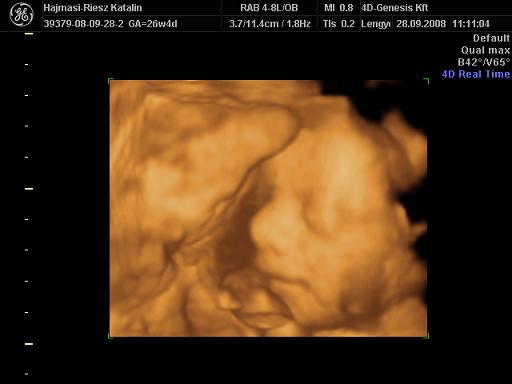

Lányok, kit hoztam?? :lol:

Kép

Mit mondjak, szuper élmény volt, nagyjából egy órát töltöttünk bent, nem volt utánunk senki :wink: Martin szép nagyot nőtt, 940 g, azt mondták, ha ilyen ütemben nő, kb 3500 g lesz mire születik! Ezzel abszolút ki is egyeznék :D Mindene rendben van, mintaszerű,csodálatos baba, édesen rángatta a köldökzsinórt megint, egyszer meg spontán bekapta a lábát :lol: Jó nagy tappancsunk van, most 5 cm-es :wink: Készült 58 kép CD-re, meg DVD és egy papír kép.

Szóval,nagyon-nagyon elégedett vagyok és abszolút pozitív volt az élmény, a szakszerűség és a törődés!!! :D